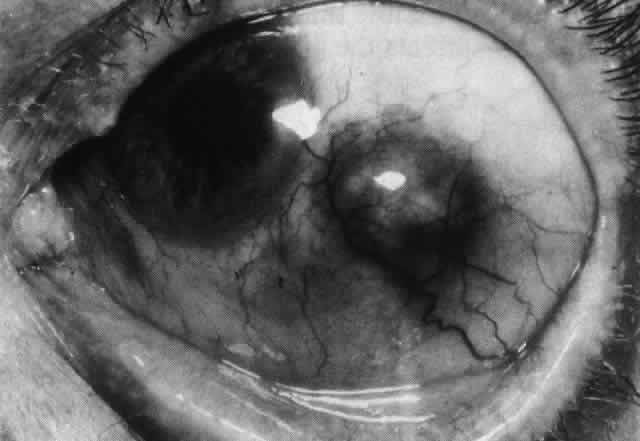

Simple and nodular episcleritis differ in their clinical courses, but in both the edema and infiltration are entirely within the episcleral tissues. The sclera is not involved. The maximum congestion is in the superficial episcleral network, with some slight congestion of the conjunctival vessels and deep episcleral vessels (Fig. 10). The intraocular structures are not involved in either variety, nor is the visual acuity affected. Anterior segment fluorescein angiography reveals a normal vascular pattern but a very rapid flow rate, with the whole transit of the dye being completed within 2 or 3 seconds (Figs. 11 and 12).

Fig. 10. Maximum congestion in the superficial vascular plexus in episcleritis. The conjunctival and deep episcleral networks are separated from the deep plexus by edema and infiltration in the episcleral tissue. (Watson PG, Hayreh S, Awdry P: Episcleritis and scleritis. Br J Ophthalmol 52(3):278–279, 1968)

The redness of simple episcleritis may be intense, varying from a fiery-red or a brick-red discoloration to a mild red flush, but it does not have the bluish tinge that is seen in scleritis. The distribution is usually sectorial but can involve the whole anterior segment of the globe. The episcleral vessels are engorged but retain their normal radial position and architecture (Figs. 13 and 14; Color Plate 1A). In simple episcleritis, there is a diffuse edema of the episcleral tissues. These tissues are sometimes infiltrated with gray deposits that appear yellow in red-free light. Surprisingly, the eye is rarely tender to the touch.

Fig. 13. Infiltration of the episclera in which the superficial episcleral vessels show maximal congestion. Conjunctival vessels are slightly congested, as is the deep episcleral plexus, whose irregular criss-cross pattern can be seen deep to the radially arranged superficial episcleral plexus.

Fig. 14. Diffuse inflammation. Superficial vessels are maximally engorged and retain their radial pattern and architecture. (See Figures 27 and 34.) (Watson PG: Connective tissue disorders and the eye. In: Recent Advances in Ophthalmology, Vol 5, pp 214–277. London, Churchill-Livingstone, 1975)